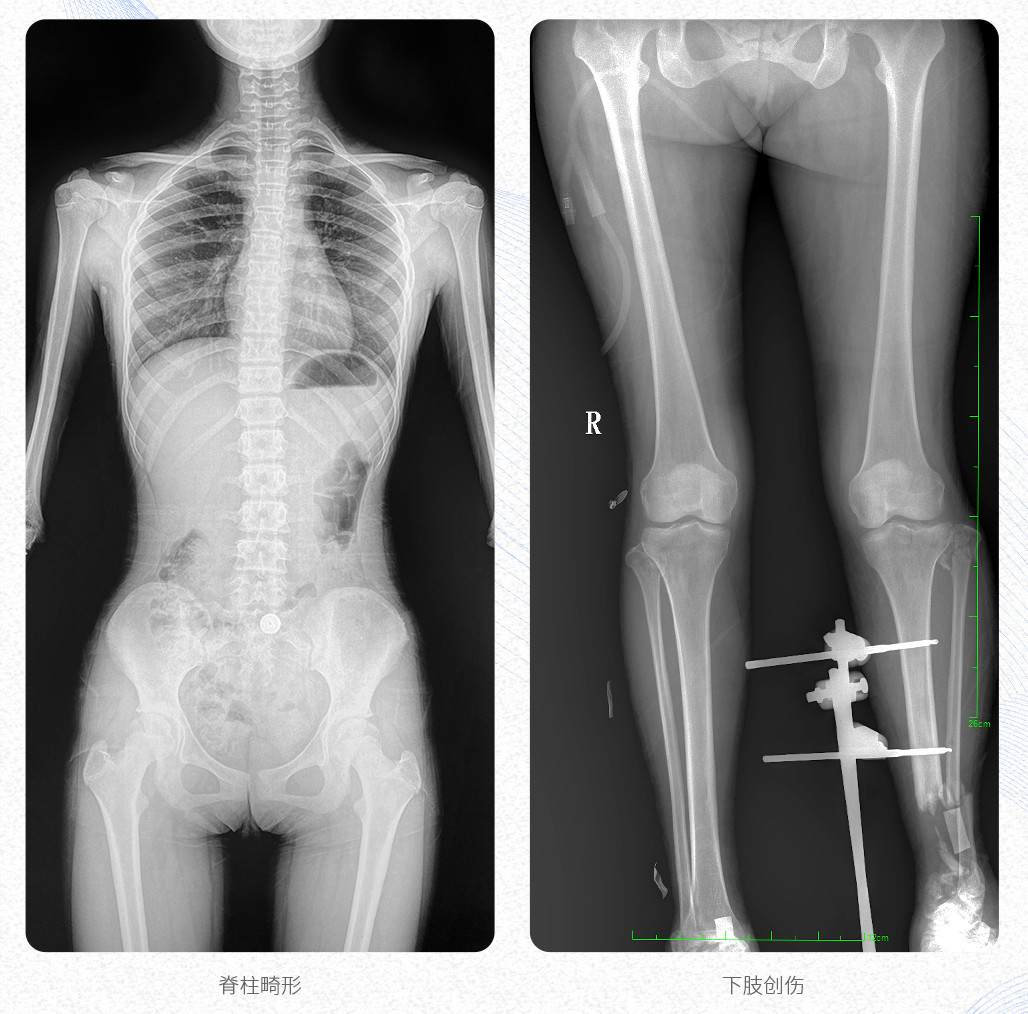

新品PLX8600大視野平板動態(tài)DR產(chǎn)品說明:

? ? 普愛醫(yī)療新推出自主研發(fā)的大視野平板動態(tài)DR——PLX8600,專為臨床大視野需求打造,圖像不拼接,可有效簡化影像科室檢查流程,提升工作效率,提高診斷精度,降低臨床拍攝劑量。